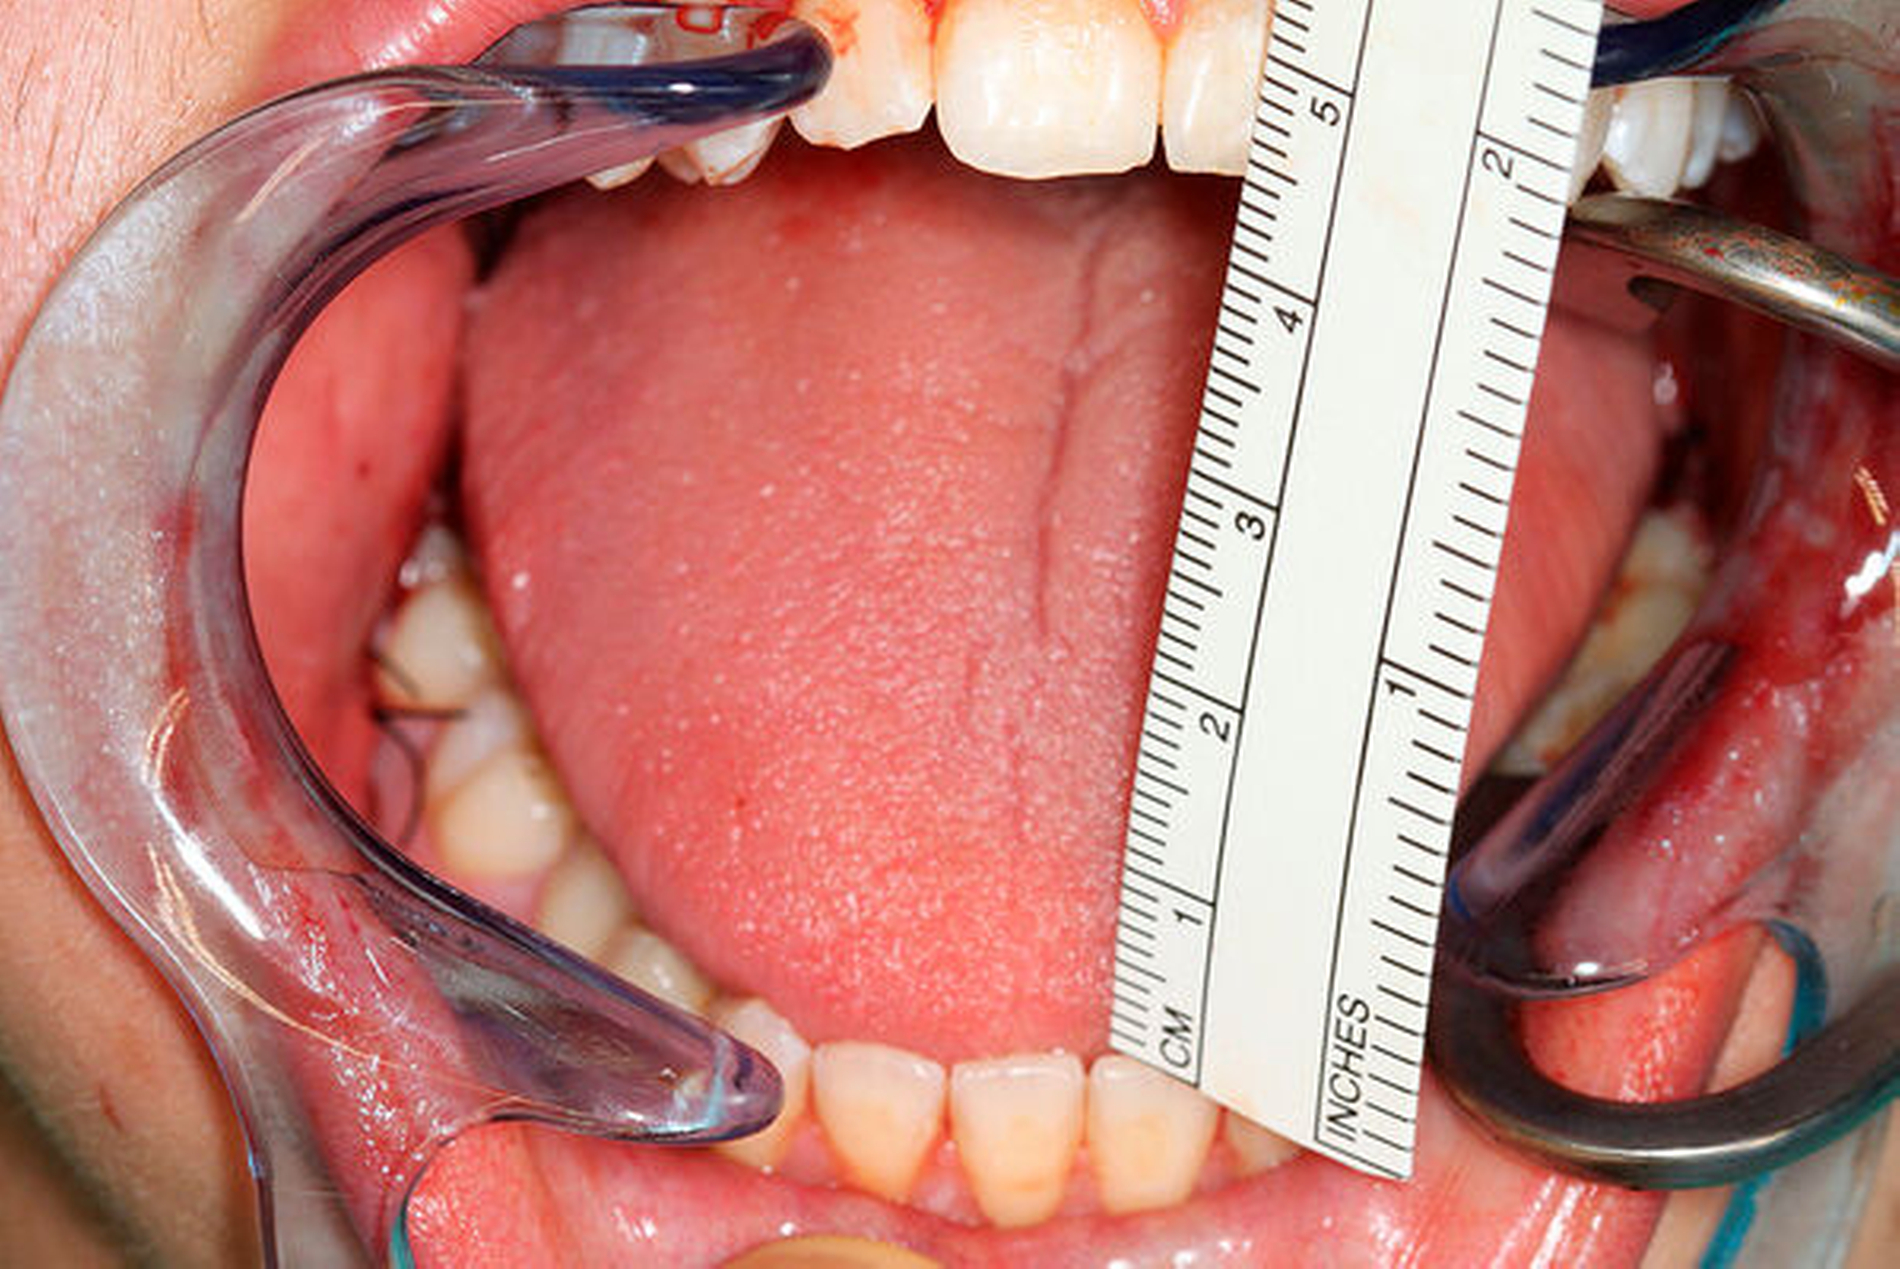

Präoperativ führten wir zur exakten Eingriffsplanung eine Computertomografie durch. Hier zeigte sich erneut die ausgeprägte Verlängerung der Fortsätze (Abbildung 5). Intraoperativ konnte beim Patienten nach beidseitiger Resektion bereits eine SKD von 44 mm erreicht werden (Abbildung 6). Die Weisheitszahnentfernung erfolgte nun problemlos. Das postoperativ angefertigte OPG zeigt die Resektionsflächen beidseits (Abbildung 7).